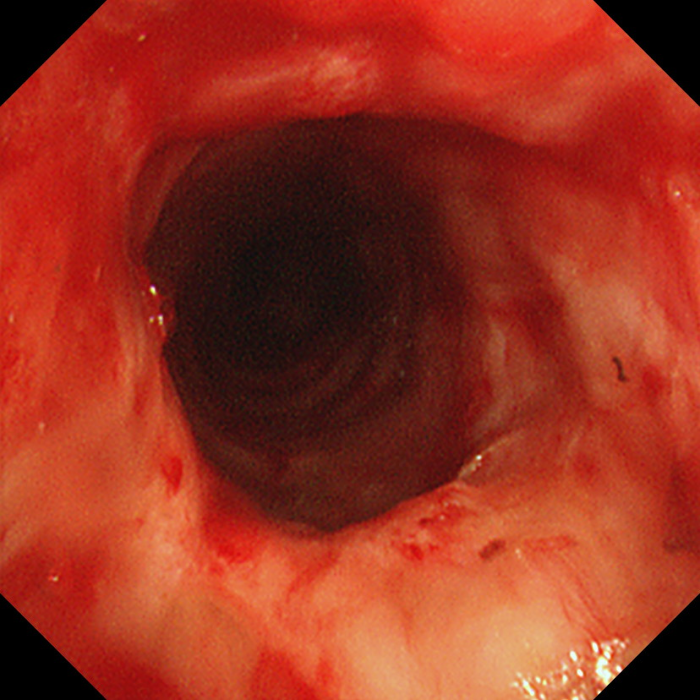

患者大气道被成功拓宽

移除支架后,团队一鼓作气,立即通过硬质支气管镜的工作通道,对增生的瘢痕组织实施了冷冻、激光烧灼及镜下喷药等综合治疗,有效拓宽了患者的大气道,重建了通畅的“生命通道”。整台手术过程流畅,团队成员配合默契,患者生命体征平稳。术后,患者安全返回病房,自觉呼吸困难、咳嗽等症状均得到明显改善。